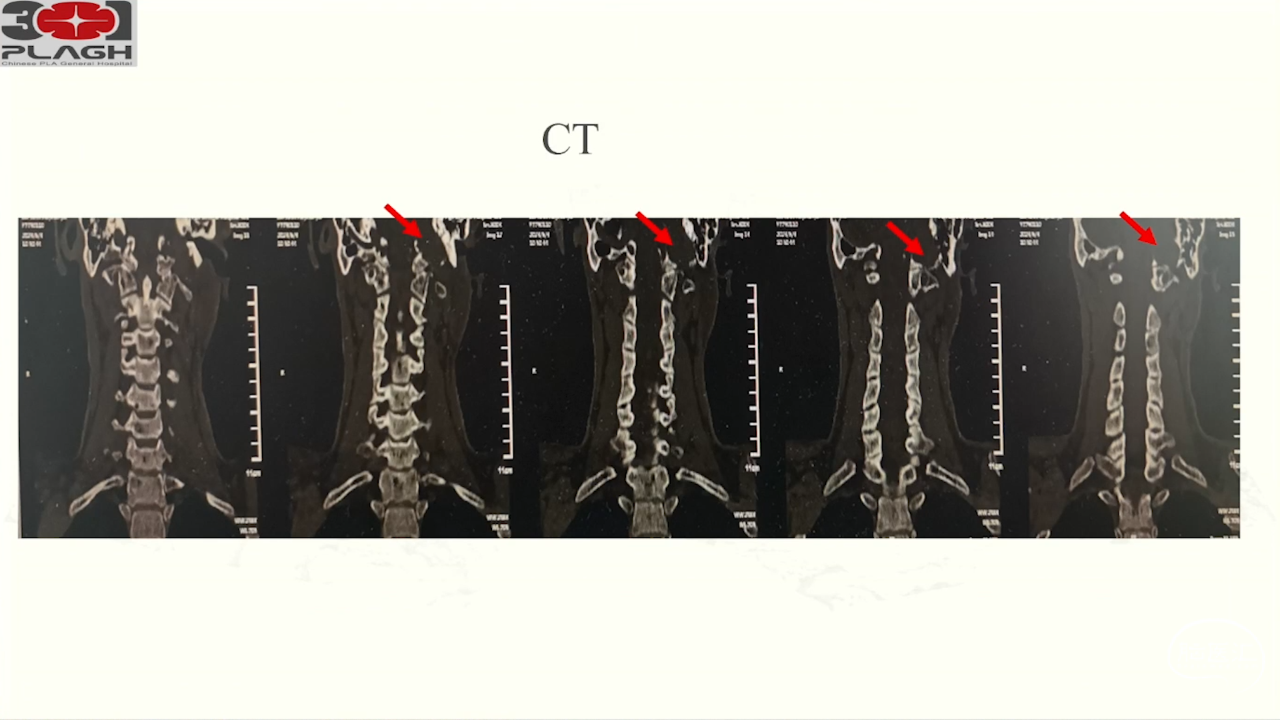

卜博教授:颈静脉孔区肿瘤:解剖及156例经验

颈静脉孔区肿瘤充分显露是硬道理。肿瘤越大,工作通道越宽。颈静脉孔扩大越明显,开放颈静脉孔越容易。